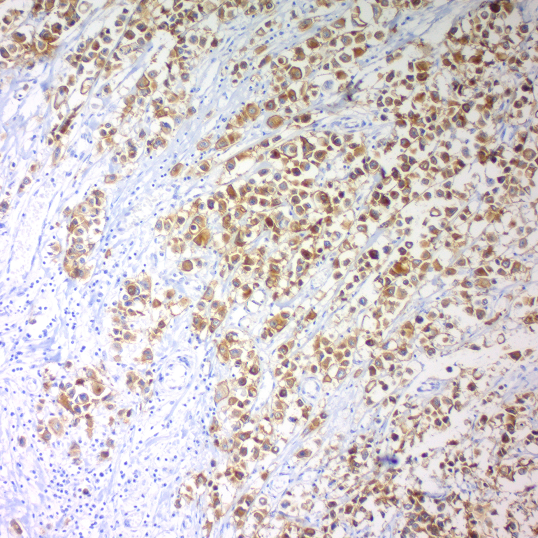

c-erbB-2 Oncoprotein; Clone SP3

Positive Control: Breast carcinoma.

Cellular Localization: Cell membrane.

Specificity: c-erbB-2 is a receptor tyrosine of the c-erbB family. It is closely related in structure to the epidermal growth factor receptor. C-erbB-2 oncoprotein is detectable in a proportion of breast and other adenocarcinomas, as well as transitional cell carcinomas.